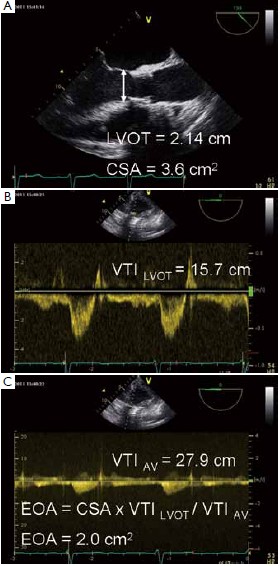

Aortic valve area calculation is an indirect method of determining the area of the aortic valve. The calculated aortic valve orifice area is currently one of the measures for evaluating the severity of aortic stenosis. ... Read Article

The aortic valve is equal, is used to determine EOA. Stroke volume in Doppler echocardiography is calculated as cross-sectional area (CSA) multiplied by the average flow velocity After surgical aortic valve replacement (sAVR), the Research Highlight ... Fetch Full Source